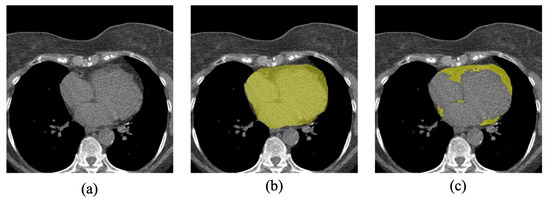

2.1. Data Set-Up